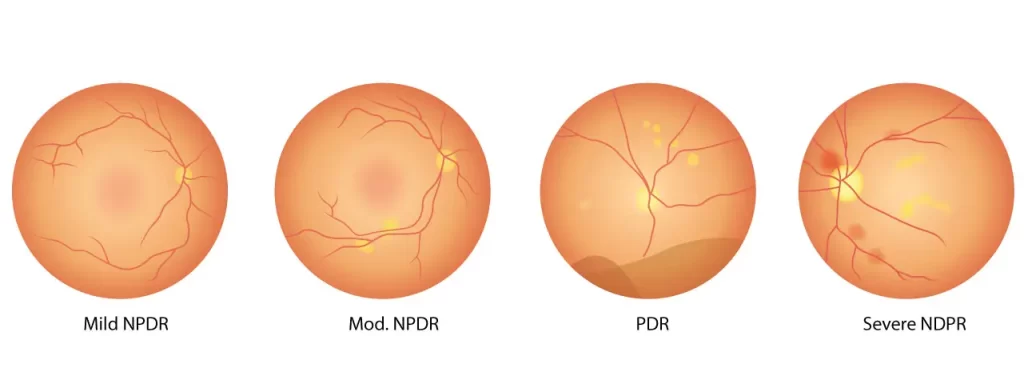

يعتمد سبب اعتلال الشبكية السكري على النوع:

- اعتلال الشبكية بسبب السكري غير التكاثري: إنه ناجم عن استجابة شبكية العين لمستويات السكر المرتفعة في الدم، حيث لا يوجد نمو في الأوعية الدموية الجديدة، لذلك فإن الحالة يمكن أن تتحسن في حال تم التحكم في مستويات السكر في الدم وضغط الدم والكوليسترول بشكل جيد.

- اعتلال الشبكية السكري التكاثري، هنا يحصل نمو في الأوعية الدموية الجديدة بشكل غير طبيعي، لذا يمكن أن يتسبب هذا في النزيف داخل العين وتشكل الأنسجة ندبات، مما يؤدي إلى انفصال الشبكية. في كثير من الأحيان، يمكن أن تسبب الأوعية غير الطبيعية تصاعد وارتفاع الضغط في مقلة العين، مما يؤدي إلى الزرق، وإلحاق الضرر بالعصب البصري، وفي النهاية يؤدي إلى العمى.